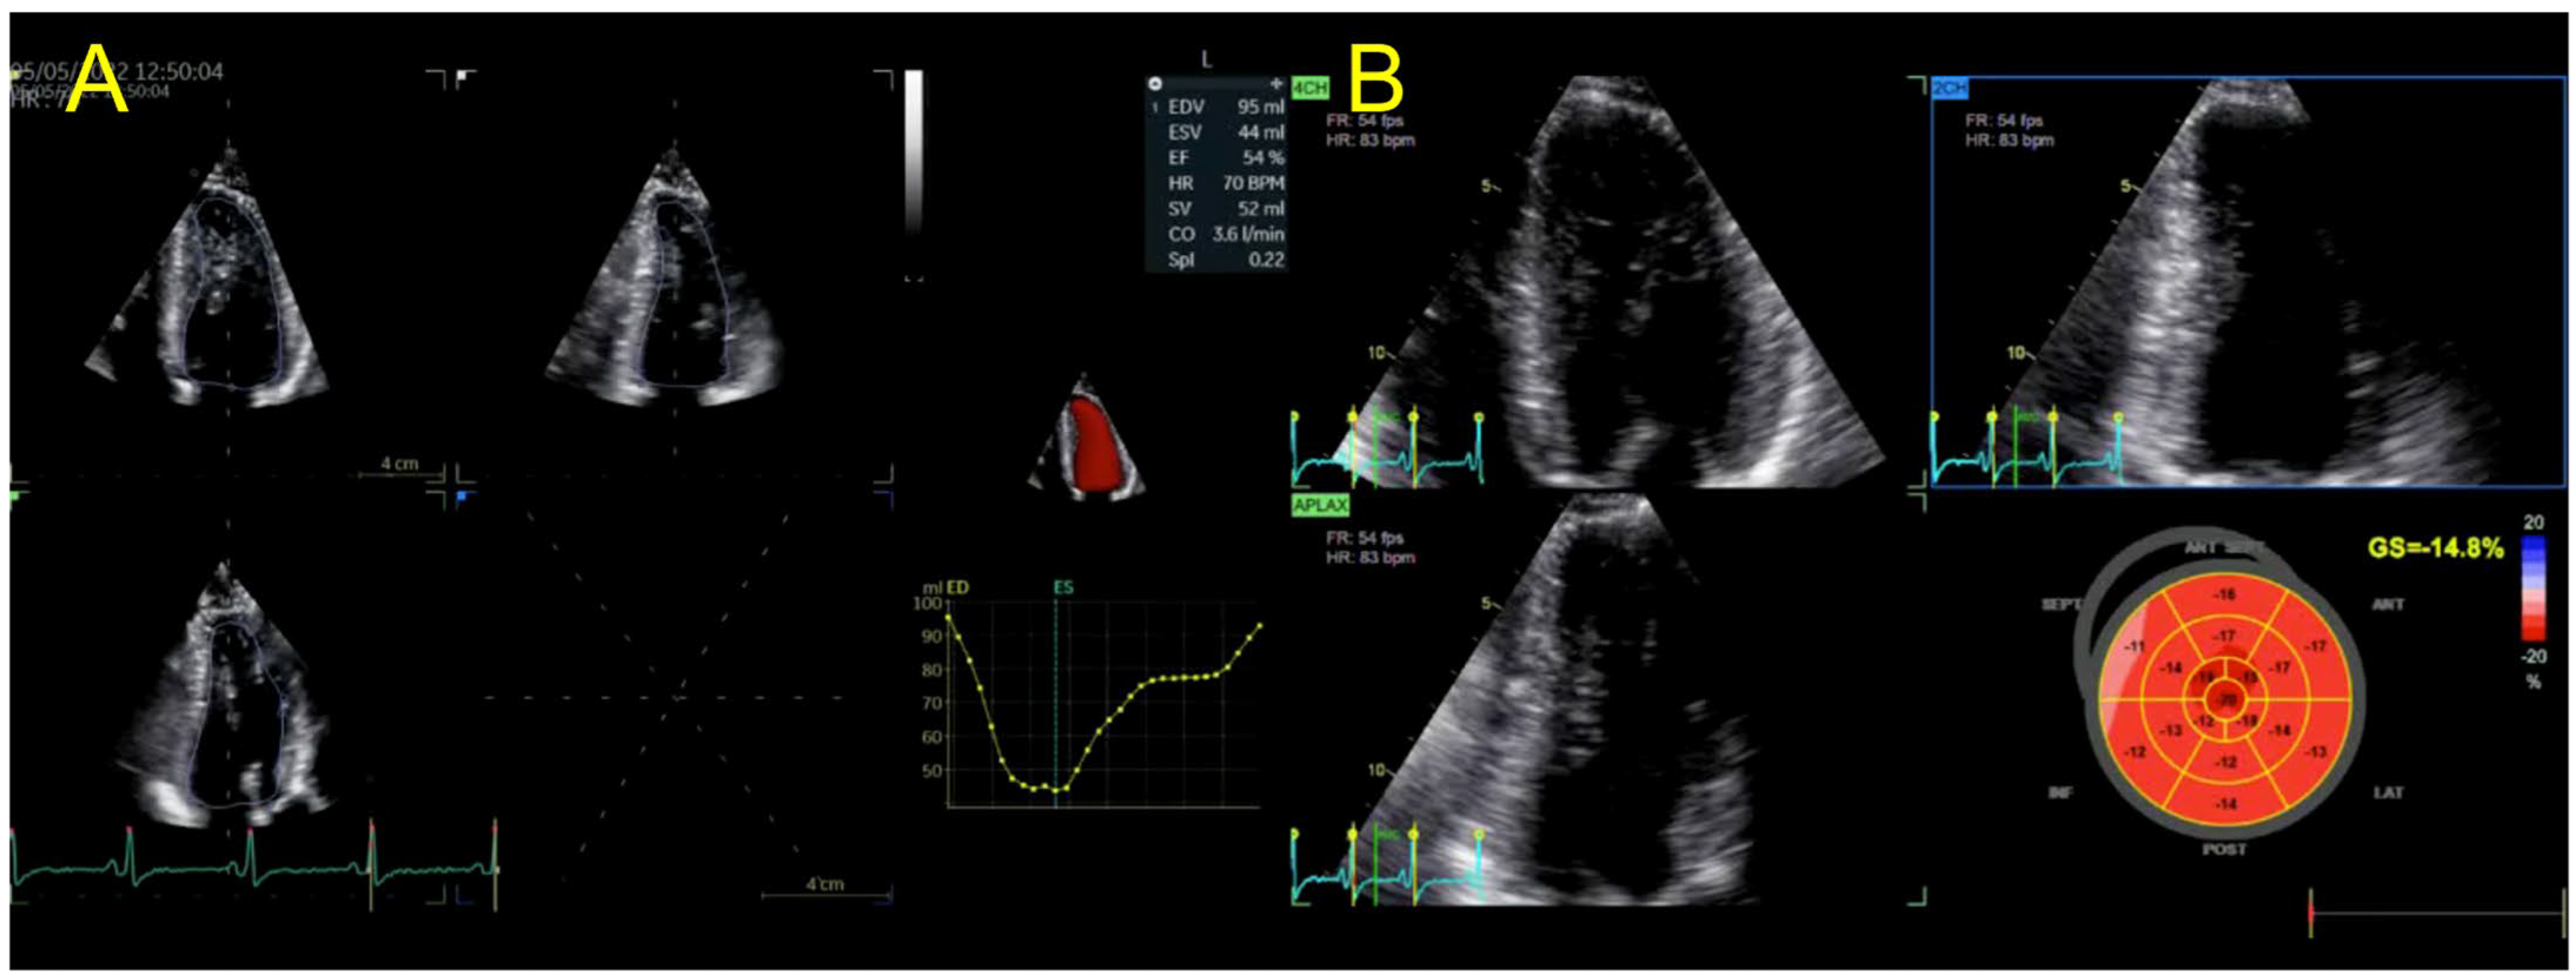

| Echocardiography | Hypokinetic non-dilated cardiomyopathy LVEF = 42% Mild mitral regurgitation IAS aneurysm | Hypokinetic non-dilated cardiomyopathy LVEF = 34% Mild mitral regurgitation IAS aneurysm | Left ventricular concentric hypertrophy LVEF = 54% |